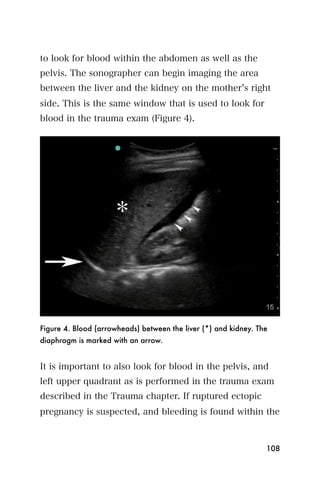

1. No baby is seen in the uterus.

2. Blood is seen in the pelvis and possibly between the

liver and kidney.

If a baby is seen in the uterus, there is probably not an

ectopic pregnancy. Blood in the pelvis or abdomen

means that the ectopic pregnancy has ruptured, and the

mother will need immediate surgery to avoid

complications. Bleeding from ectopic pregnancy can be

life threatening.